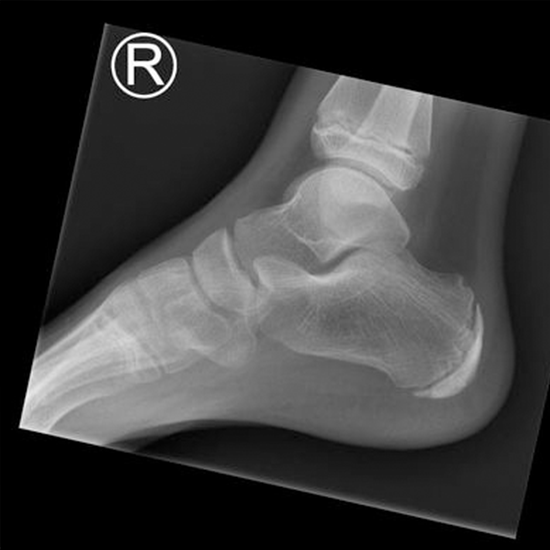

What is an X-ray Both Calcaneum LAT View Test?

X-rays are used to see the calcaneus (the bone of the heel) and the soft tissues around it (skin and muscles). This view lets doctors check for bone damage and figure out how big and where fractures are.

The doctor will give you this test to find out if your heel bone (calcaneus) is broken or fractured and check how it heals after it has been set.